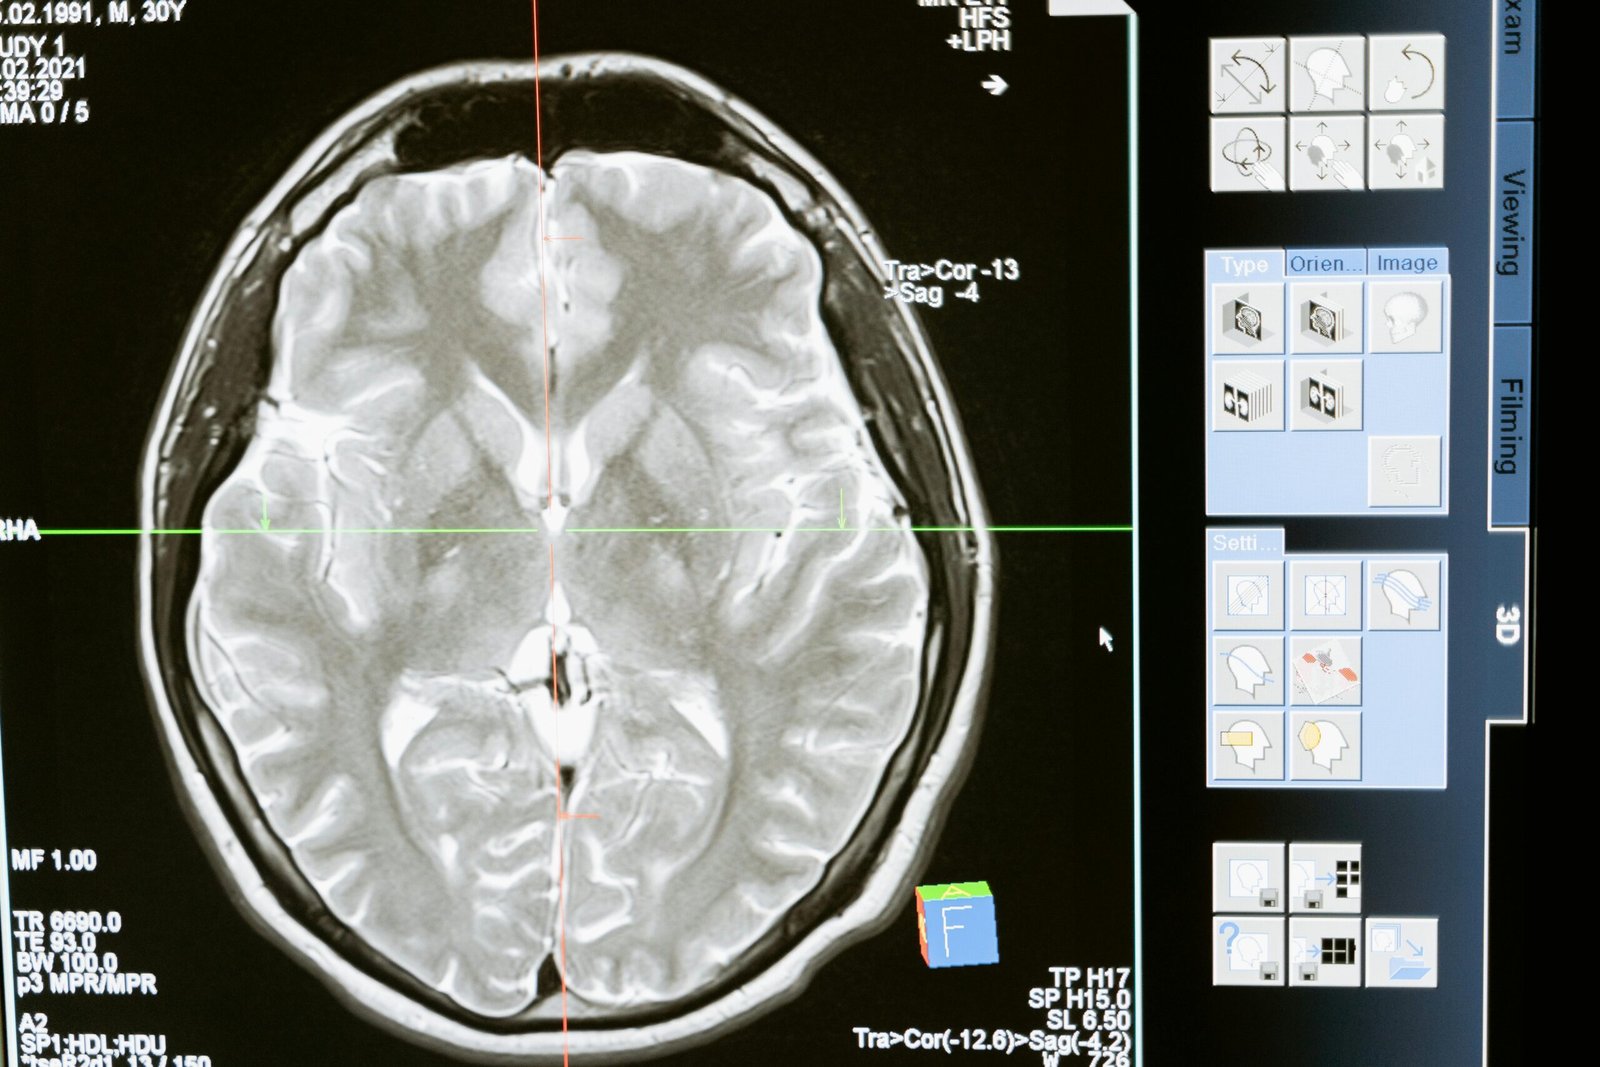

Os radiofármacos são medicamentos associados a material radioativo utilizados em diagnósticos e tratamentos, especialmente em casos de câncer, doenças cardíacas, neurológicas e de tireoide. Graças a eles, exames como a cintilografia possibilitam diagnósticos mais precisos e tratamentos mais eficazes.